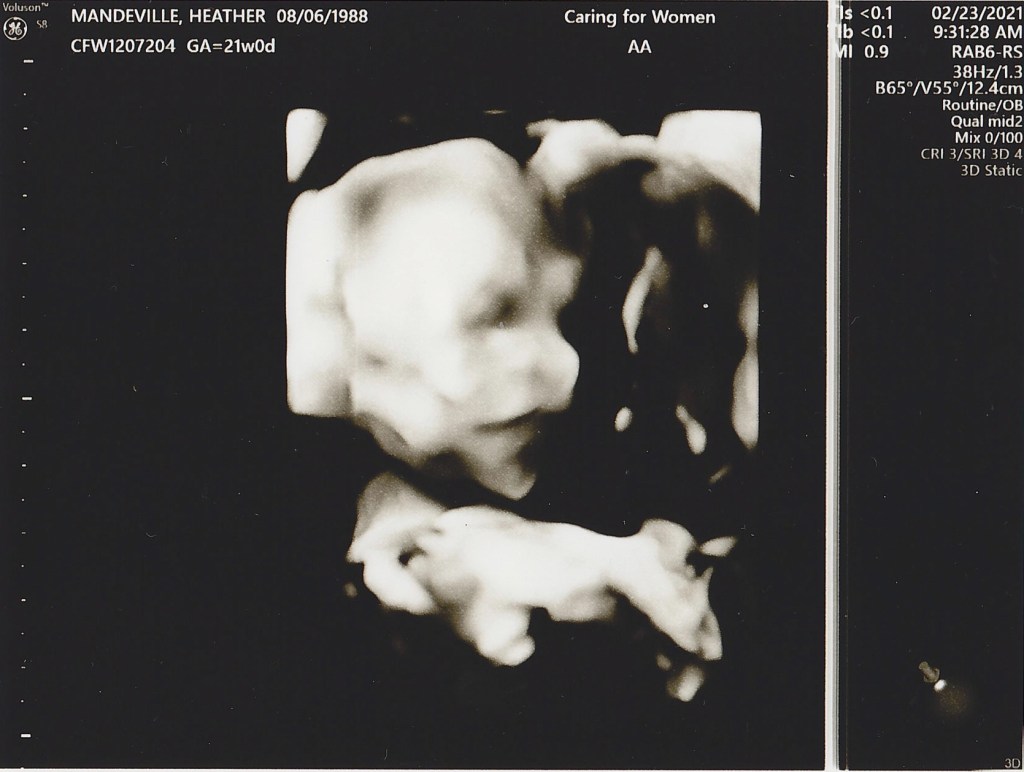

20 week sonogram

IT’S A BOY!! We found out today we are having a boy and we could not be more excited! Everything is looking good, Heather and the baby are healthy and he is progressing as expected. Now we get to start really planning to welcome him into this world, so many things to do in the next 20 weeks!